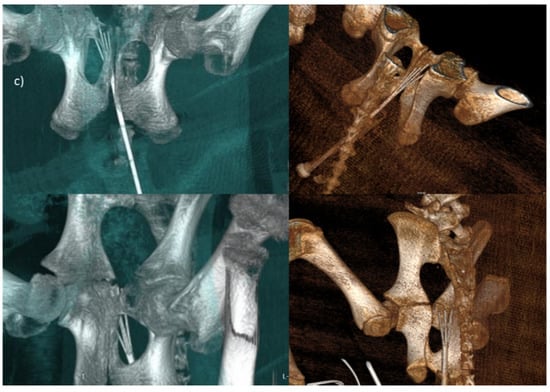

2.3.2. Endoscopic Trans-Oral and Trans-Anal Approach

2.4. Imaging Data Analysis